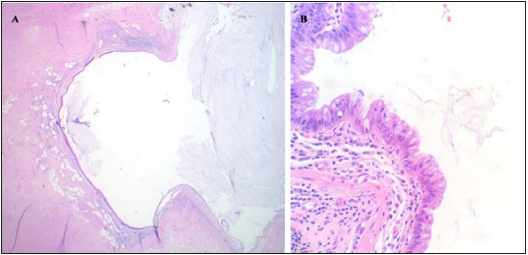

An urgent exploratory laparotomy was performed and revealed multiple adhesive bands and a dilated cecum with torsion intraoperatively. Right hemicolectomy was performed thereafter. The pathologic report showed a low-grade appendiceal mucinous neoplasm that focally invades the muscularis propria, uninvolved margins, no high-grade cytologic features, 0/10 lymph nodes involved (Figure 3). Patient developed postoperative ileus; the NG tube was kept in place for decompression. However, she pulled out the NG tube accidentally in day 2 post-operation, and developed hypoxia. Aspiration pneumonia was considered, and she was treated with piperacillin-tazobactam. The NG tube was replaced, and the ileus resolved in day 6 post-operation. She discharged back to the personal care home facility after completing 7 days of antibiotics. She followed up with General surgery and Oncology in the outpatient clinic. No chemotherapy was planned due to early stage of the disease and there was plan for active observation.

Figure 3:Histopathologic slides showed low-grade appendiceal mucinous neoplasm (A). The higher power view showed a single layer of epithelium with focal tufts, but no high-grade cytologic features or infiltrative growth pattern were identified (B).

There is little consensus on the optimal choice of procedure (appendectomy versus right hemicolectomy) and the approach (laparoscopic versus laparotomy) in treating LAMN. The incidence of regional lymph node spread is less than 2% with localized well differential appendiceal mucinous neoplasm, therefore, simple appendectomy is sufficient for tumors exhibiting only local involvement [9]. Right hemicolectomy is considered if there is positive margin involvement after appendectomy, and for tumors involving the peri-appendiceal area, tumor size of 2cm or larger, high grade histology, or for tumors that invade the muscularis propria [10]. The right hemicolectomy was performed to our patient based on the intraoperative findings. A LAMN without lymph node metastasis was confirmed by pathology.